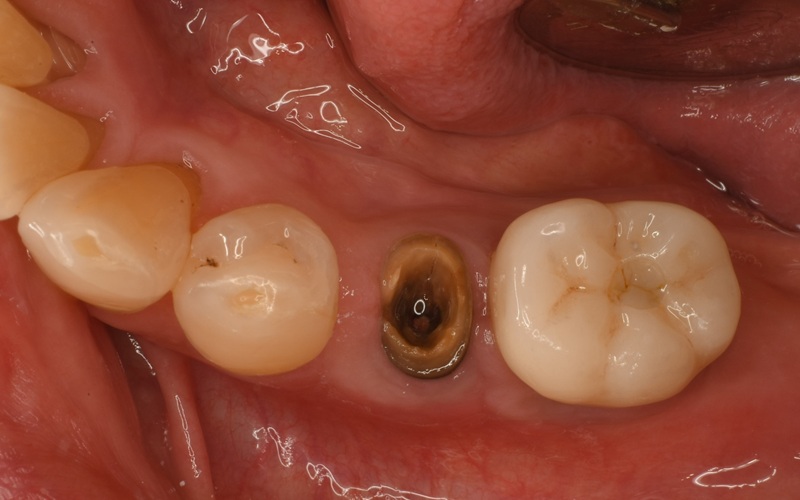

Case7

術前

術中

術後

| 治療名 | 抜歯即時インプラントとソケットリフトによる上顎臼歯部の修復症例 |

|---|---|

| 治療説明 |

歯の根が破折していたため抜歯が必要となり、患者さんとご相談のうえ、インプラントによる治療を選択しました。 ただし、インプラントを支える骨の高さが不足していたため、**上顎洞に骨を足す“ソケットリフト”**を併用し、安全にインプラントを埋入しました。 |

| 治療回数・期間 | 約3ヶ月 |

| 副作用とリスク |

・入れ歯や従来のブリッジと比べて、治療期間が長くなる傾向があります。 |

| 料金(税込) | 小規模GBR:110,000円 ソケットリフト:165,000円 インプラント一次手術:220,000円 二次手術:55,000円 上部構造〈セラミック〉:165,000円 合計:715,000円 |